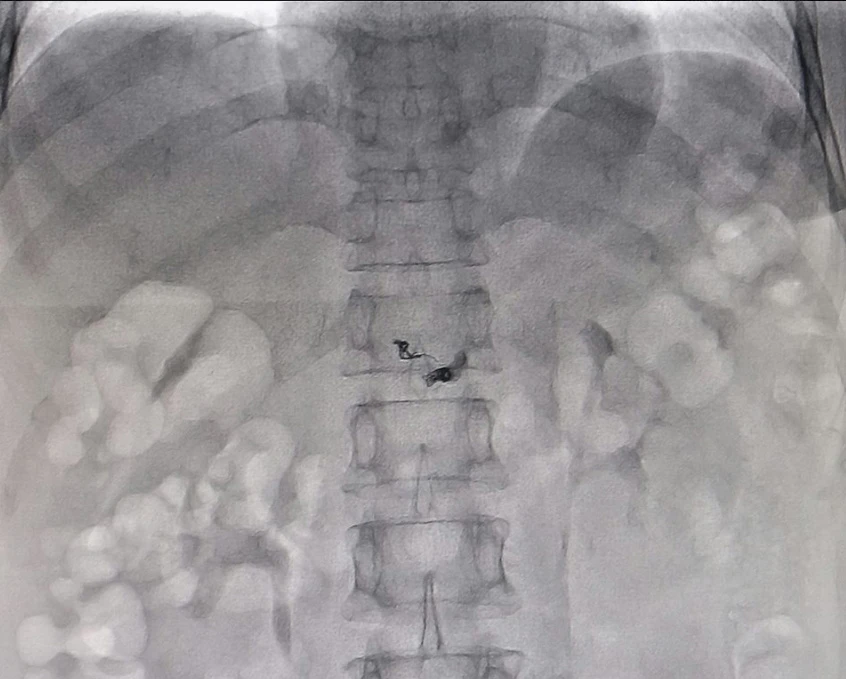

Các bác sĩ thực hiện can thiệp gây tắc lỗ dò. Ảnh: CTV

Các BS đã chụp kỹ thuật số xóa nền (DSA). Kết quả hình ảnh xác định bà T. bị Hemangioma ở tụy, kèm theo rò động mạch tụy lưng vào tĩnh mạch cửa. Sau đó, các BS khoa Ngoại tổng quát và Trung tâm Can thiệp tim mạch quyết định can thiệp điều trị cho bà T. bằng DSA, can thiệp nội mạch gây tắc mạch nuôi u bằng hạt P.V.A. Sau bốn giờ can thiệp, vùng tổn thương đã được khắc phục hoàn toàn. Sức khỏe bà T. dần ổn định.